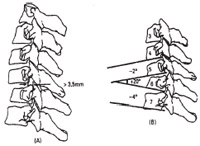

Para o segmento cervical baixo da terceira vértebra cervical à transição cervicotorácica, a distância de deslocamento nas radiografias de perfil não deve ultrapassar 3,5mm e a angulação entre dois níveis adjacentes não deve ser maior que 11º (figura 5). Valores acima desses indicam instabilidade do segmento cervical e necessitam de tratamento. |

Fig. 5 A - Medida esquemática da distância entre as linhas posteriores dos corpos vertebrais. B – Medida do ângulo formado entre as linhas inferiores dos corpos vertebrais. |